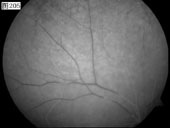

[组图]优秀眼底图片奖网上评选活动启动         ★★★

优秀眼底图片奖网上评选活动启动

优秀眼底图片奖应征作品展示